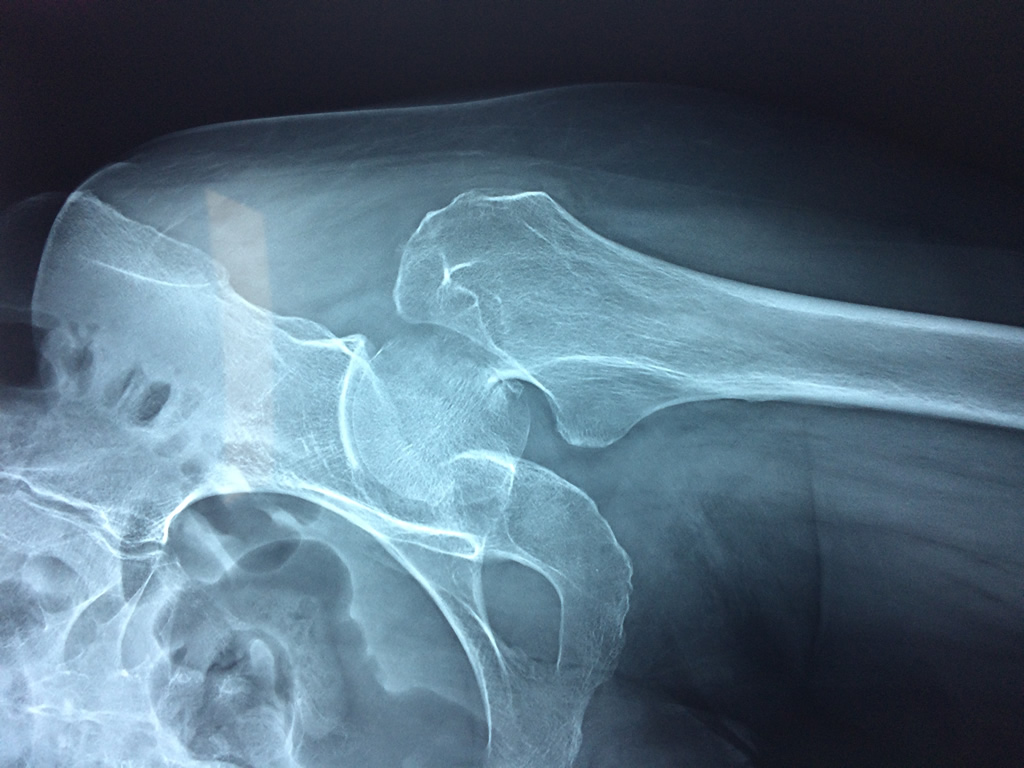

Húmero - Cadera